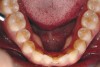

Figure 4a  Corticotomy SFOT. A 42-year-old male presented with a history of extraction orthodontic therapy (A). Incisors were too upright and had severe incisal wear. He was concerned about esthetics of the worn teeth and his insufficient lip support.

Figure 4a

Figure 4b  Progress photo and panorex 9 months after corticotomies were performed on Nos. 6 through 11 (B and C). Previous extraction sites were reopened orthodontically to improve function and fill lip support. Incisal edges were restored provisionally with composite resin. Note that despite the creation of adequate spaces to replace missing teeth, there is inadequate room for placement of dental implants because of severe tipping of all the anterior teeth. Osteotomy SFOT may have been a better choice because it would have allowed needed alveoloskeletal correction (without excessive tipping) instead of the primarily dentoalveolar correction common in corticotomy SFOT. Restorative dentist: Brad Jones, DDS.

Figure 4b

Figure 4c  Progress photo and panorex 9 months after corticotomies were performed on Nos. 6 through 11 (B and C). Previous extraction sites were reopened orthodontically to improve function and fill lip support. Incisal edges were restored provisionally with composite resin. Note that despite the creation of adequate spaces to replace missing teeth, there is inadequate room for placement of dental implants because of severe tipping of all the anterior teeth. Osteotomy SFOT may have been a better choice because it would have allowed needed alveoloskeletal correction (without excessive tipping) instead of the primarily dentoalveolar correction common in corticotomy SFOT. Restorative dentist: Brad Jones, DDS.

Figure 4c